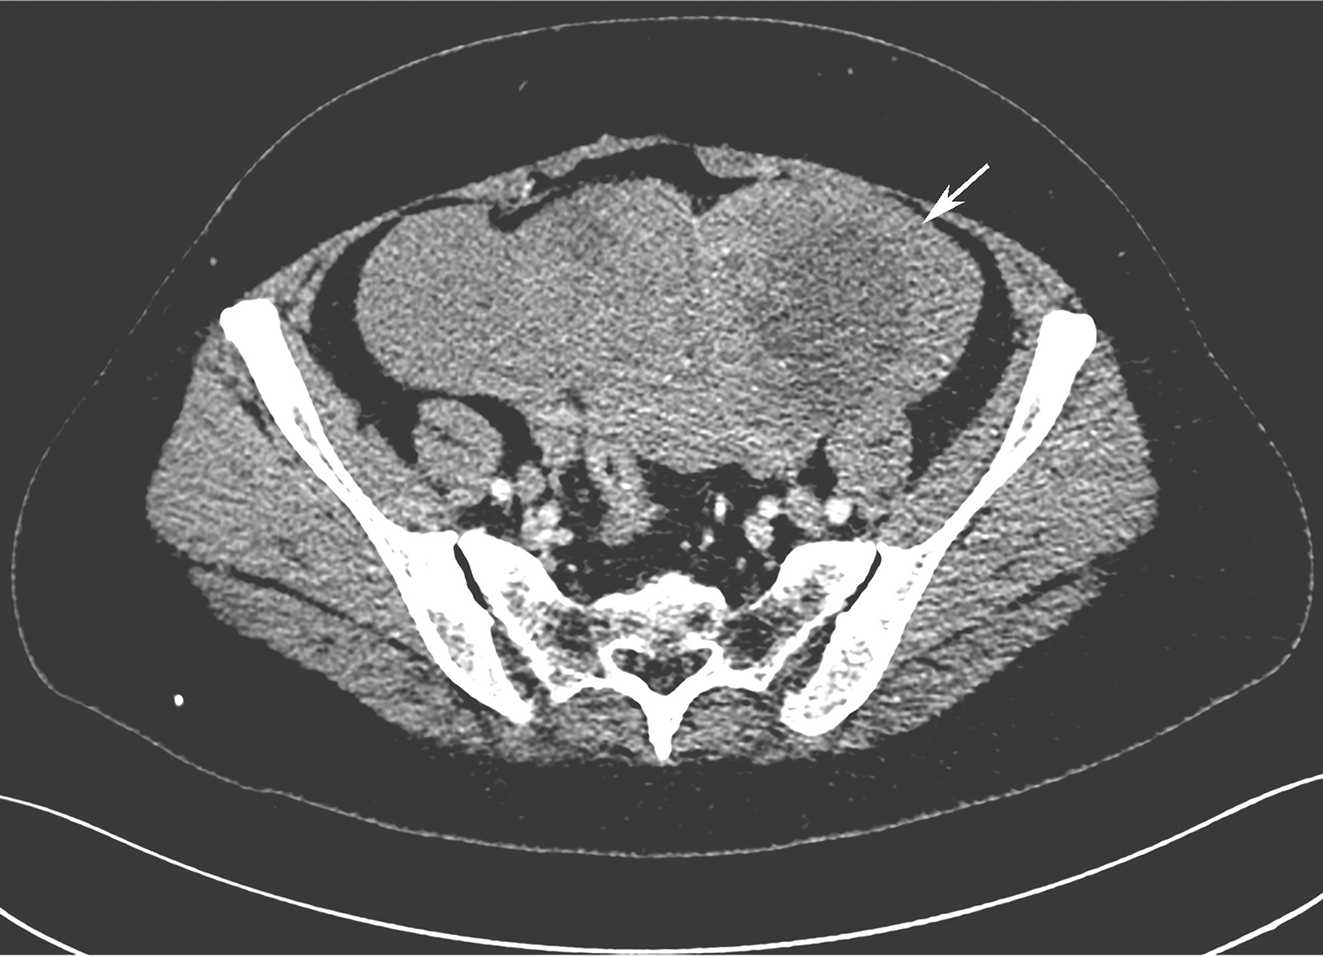

肿瘤标志物:CEA、CA199、CA125未见异常。

全腹增强CT:①盆腔积液、积血,盆腔软组织密度肿块影,最大截面约15cm×9cm,与子宫分界不清,增强扫描呈明显不均匀强化,内见血管影(图1);②左肾中上份见巨大不规则占位,最大截面约15cm×10cm,内散在点状钙化灶,增强扫描呈明显不均匀强化,左右肾受压下移(图2)。

图1增强CT示盆腔巨大占位